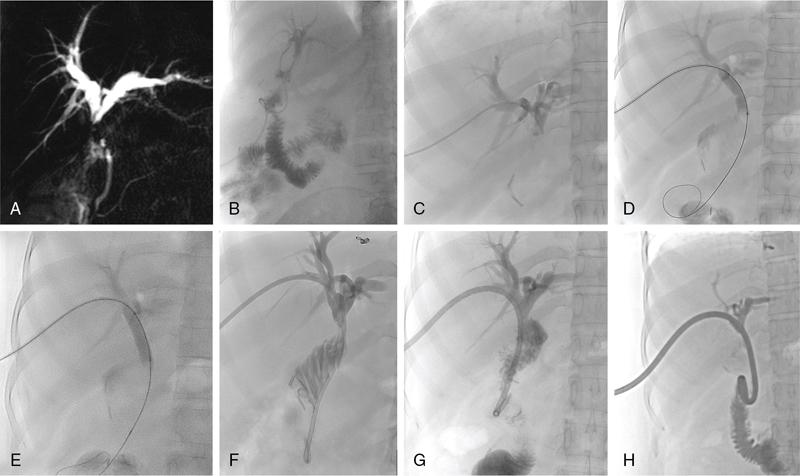

The aetiologies for BBS include iatrogenic, autoimmune, infectious, inflammatory and congenital causes. The most common cause is an iatrogenic stricture developing after cholecystectomy (0.5%–0.7% of cholecystectomies), liver transplantation (10%–40% of liver transplantation surgeries) and pancreatobiliary surgeries. Treatment varies based on the aetiology and the type of stricture. Differentiation of benign and malignant stricture is essential prior to percutaneous intervention. The diagnosis of BBSs should be made carefully by a combination of clinical history, cross-sectional imaging studies and surgical details. These patients can be asymptomatic presenting with altered laboratory parameters or have clinical symptoms such as anorexia, jaundice, fever with chills due to cholangitis and abdominal pain. In chronic cases, patients may also develop secondary biliary cirrhosis and subsequently liver failure. Bile leaks are associated mostly with cholecystectomy, hepatectomy and pancreatobiliary surgeries. Bile leak results in biliary peritonitis, biloma, abscess and increases the risk of septicemia. Although, surgery is the mainstay for the management of BBSs, the role of endoscopy-guided management is now considered equally safe and effective. Percutaneous management is indicated in patients who are poor surgical candidates or those with failed or difficult endoscopic access due to unsuccessful cannulation or altered anatomy such as in a Roux-en-Y hepaticojejunostomy or a distal gastrectomy. The aim is to relieve the obstruction and then either to prepare the patient for surgery or to perform additional percutaneous interventions. In patients with bile leak, PTBD causes diversion of bile and thus allows healing of the site of leak. The most common indication is postoperative bile leak. The first step is to confirm the benign nature of the stricture. Review of clinical history, clinical examination and lab parameters is of paramount importance. History of cholecystectomy, liver transplantation or a pancreatobiliary surgery provides clues towards a benign stricture. Imaging helps in noninvasive assessment. USG, contrast-enhanced CT and MRI with MRCP are all useful and may help to characterize the stricture. A plan is to be formulated based on the imaging findings. Often bile leak is confirmed by the persistent drainage of bile in the drainage catheter. Imaging in such cases may not be needed. However, more frequently, MRI with MRCP is performed to define the anatomy of the bile ducts, anatomical variations and possible site of bile duct injury and leak. This will help plan the percutaneous interventions. Presence of ascites, biloma and liver abscesses require additional drainage. Reviewing the blood laboratory parameters and obtaining informed consent, are similar to other intervention procedures. Up to 30% of patients with non-malignant biliary strictures may have a protracted, complicated course requiring multidisciplinary management. In patients where other procedures are not suitable, percutaneous methods may be utilized. The techniques available include balloon dilatation of the stricture, percutaneous large calibre drain placement or stent placement. The steps for PTBD are the same as described previously. Benign strictures usually produce less upstream dilatation and thus 21G or 22G needle is required for the initial duct puncture. It may be difficult to internalize the drainage catheter due to dense fibrosis at the site of the stricture. In such cases an external drainage catheter should be left in situ and internalization may be re-attempted after 2–3 weeks. Few additional percutaneous procedures are performed to open these strictures as repeat surgery or endoscopic approach is difficult. Short-segment unifocal strictures respond better to balloon dilatation with short-term patency ranging from 50% to 90% and long-term patency of 56%–74%. Strictures developing in the early postop period (<1 month) after liver transplantation may be secondary to oedema or kinking of the duct and these also do not respond well to balloon dilatation. The procedure involves crossing the stricture with a guidewire, followed by balloon dilatation (Fig. 9.24.15). The diameter of the balloon chosen should be at least as large as the bile ducts proximal and distal to the obstruction and may be oversized by up to 20%–25%. Further oversizing may cause rupture leading to bleeding or bile leak. Following dilatation, a drainage catheter is usually left in situ to allow healing around the catheter. The dilatation process may be repeated at 4-week intervals to improve patency.